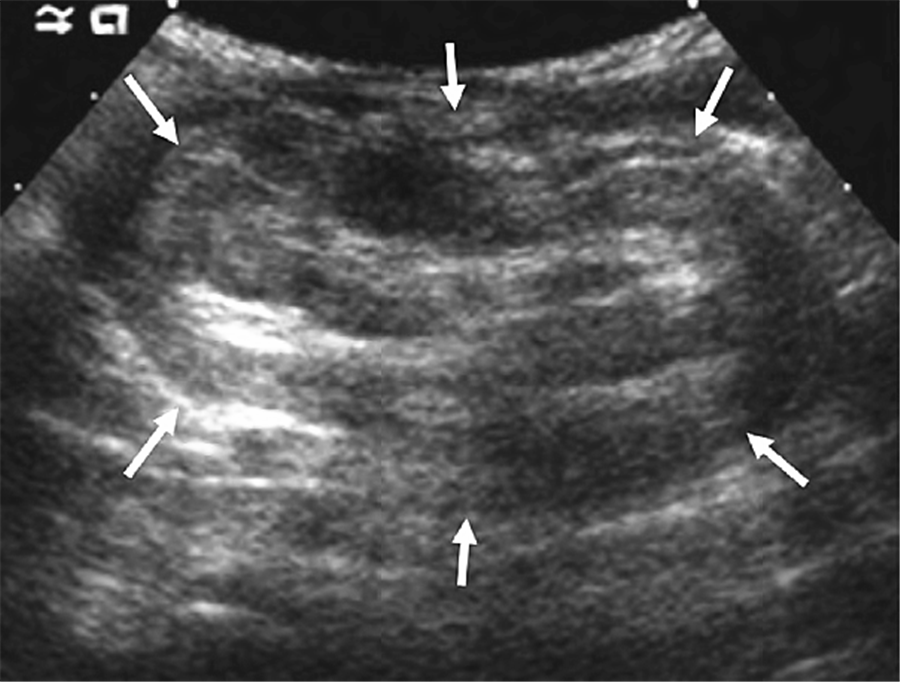

在超声上,肠套叠短轴表现为高低回声交替的环状结构,呈同心圆征、甜甜圈征、靶环征,黏膜及黏膜下层回声明显,呈高回声,而肌层呈低回声;直径可大于3cm;肠套叠长轴表现为套袖征、假肾征,特征为交替出现的高低回声带。此外,往往还可发现一些与肠套叠相关的其他表现,如梗阻部位近端小肠扩张、周边积液和负责供血的肠系膜血管位置异常、倒置等。

图16 肠套叠。长轴,假肾征,箭头所示